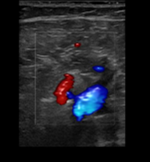

Hallazgos ecográficos

Ecografía clínica en el mismo momento de la consulta: vena poplítea derecha y vena safena derecha no compresibles imagen hipoecocicas sugestivas de tombo sugiere trombosis venosa profunda en territorio poplíteo. Se deriva a hospital.

Ecografía diagnóstica Doppler de confirmación en hospital: trombosis venosa profunda poplítea derecha.